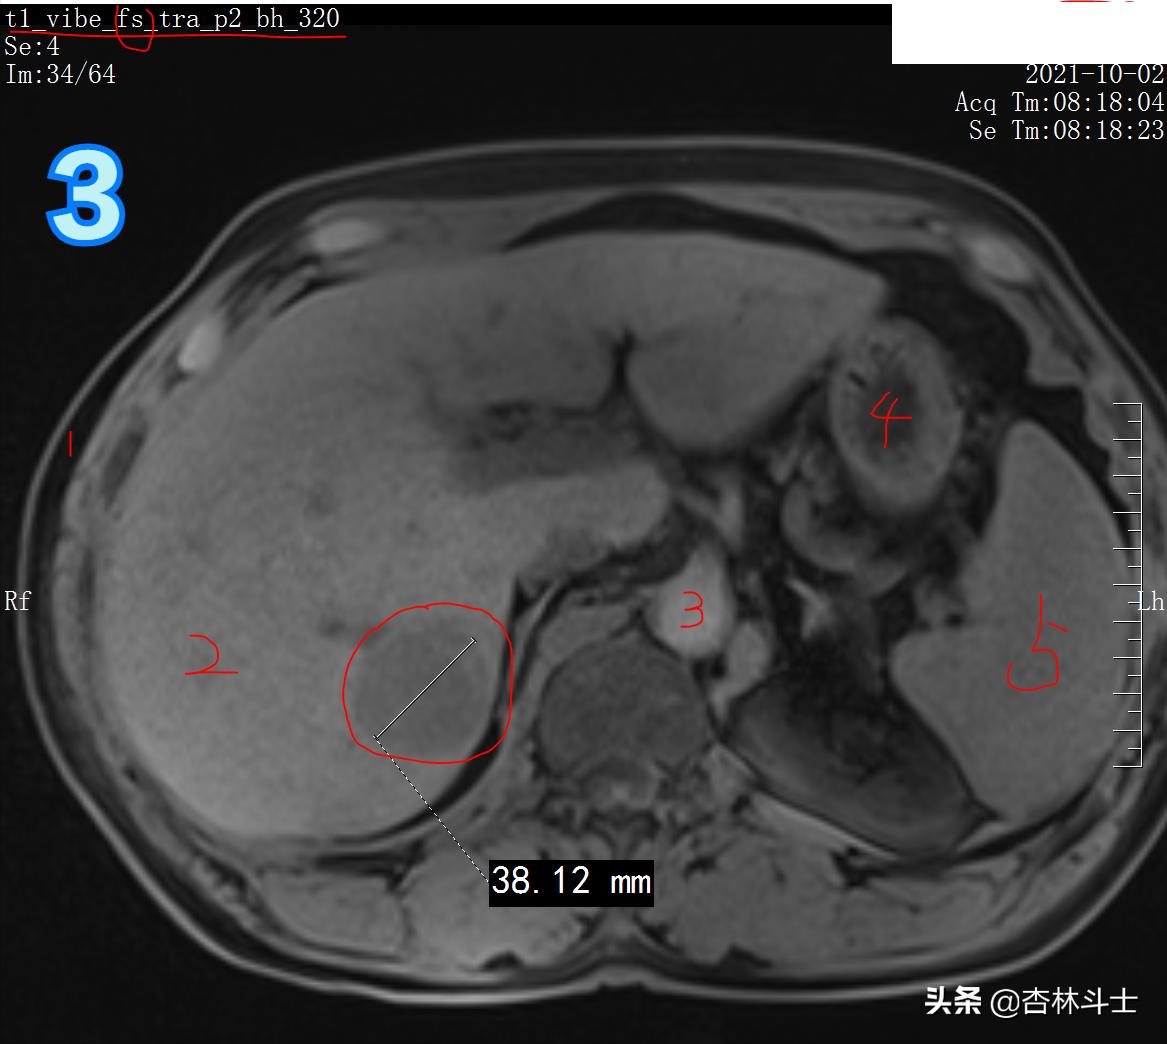

图3 T1加权压脂序列

图3 中 1、皮下脂肪 2、肝脏 3、腹主动脉 4、胃腔 5、脾脏

图1-3为T1加权图像,同一台3T磁共振机器上做的,与1月22日的信号明显不同,说明病灶里面的成分有所变化。